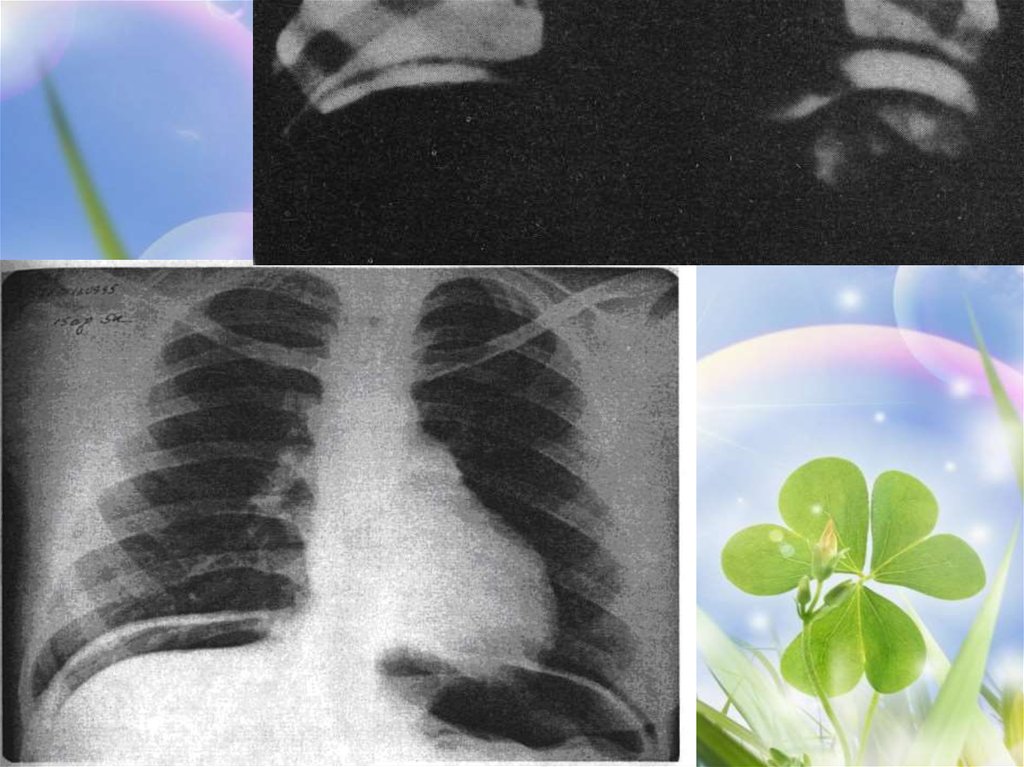

Еще более доказательно обнаружение газа на рентгенограмме

брюшной полости, сделанной в

вертикальном положении больного или на

боку.

34. клиника

36. клиника

Но газ не всегда находится в

содержимом или его может

быть недостаточно. Поэтому

этот симптом определяется

не всегда, только у 2/3

больных. Газ находится в

большей степени в желудке,

чем в ДПК.